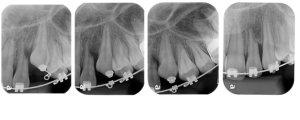

Tracionamento do canino impactado e a reabsorção grau 4 do incisivo lateral

Diferente das reabsorções radiculares induzidas pelos movimentos ortodônticos, as causadas pelos posicionamentos inadequados dos caninos ocorrem, na maioria das vezes, nos terços médios das raízes e podem ser classificadas segundo a sua severidade em:

- Grau 4 – Reabsorção severa, envolvendo a cavidade pulpar.